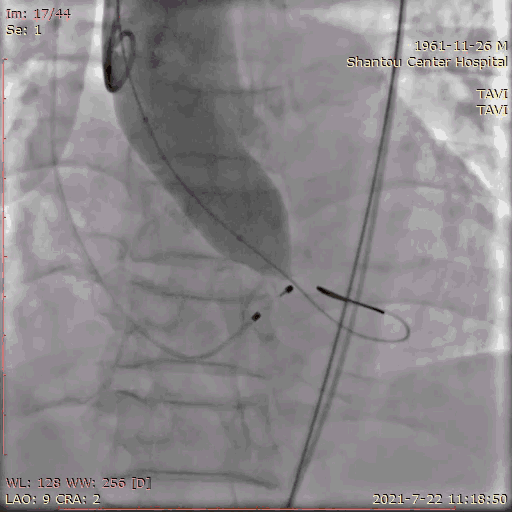

主动脉根部造影

跨瓣

180bpm起搏后打球囊,造影,撤球囊,停起搏;23球囊预扩后无漏,冠脉通畅,选择29瓣膜。

球囊预扩张

输送系统定位,标准位置释放